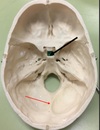

1. Identify the spaces labelled.

Anterior Cranial Fossa, Middle Cranial Fossa, Posterior Cranial Fossa

104

1. Identify the elevation. 2. What is the function of this structure?

1. Frontal Crest and Crista Galli 2. Attachment of Falx Cerebri, olfactory bulbs run lateral to it.

105

1. Foramen caecum 2. it transmits the emissary vein from the nose to the superior sagittal sinus. This has clinical importance in that infections of the nose and nearby areas can be transmitted to the meninges and brain from what is known as the danger triangle of the face.